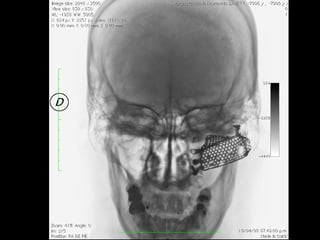

Implantes de titanio en cara

Implantes de titanioen cara Consideraciones generales en implantología